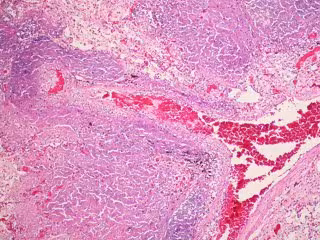

Archivo - Tuberculosis - FLICKER/ PULMONARY PATHOLOGY - Archivo